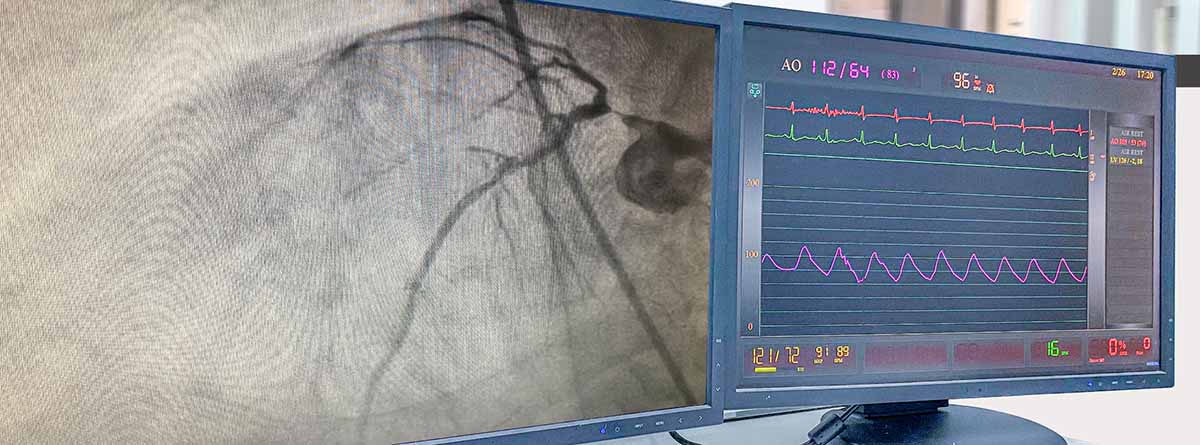

- Angiografía para el estudio de los vasos sanguíneos…

- La angioplastia y la colocación de stents para tratar oclusiones arteriales y las embolizaciones para detener sangrados o tratar malformaciones arteriovenosas, la colocación de catéteres o el cateterismo cardíaco permitiendo visualizar la circulación en las arterias coronarias y tratar obstrucciones en estas arterias.